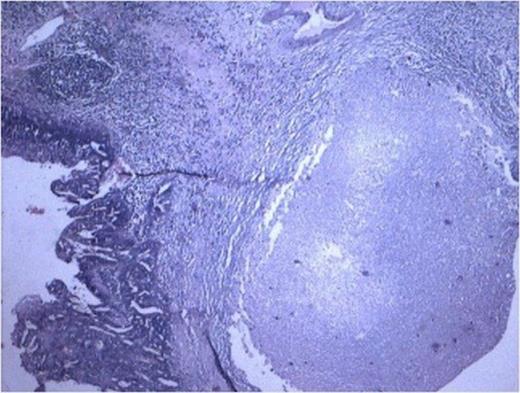

Cyst lined by metaplastic epithelium with focus of malignant squamous cell. (100x H and E stain)

Histopathology from solid portions in pelvis region showed features of moderately differentiated squamous cell carcinoma (Fig 3). The tumor was not involving retroperitoneal soft tissue including renal vessels, Gerota’s fascia and lymph nodes.